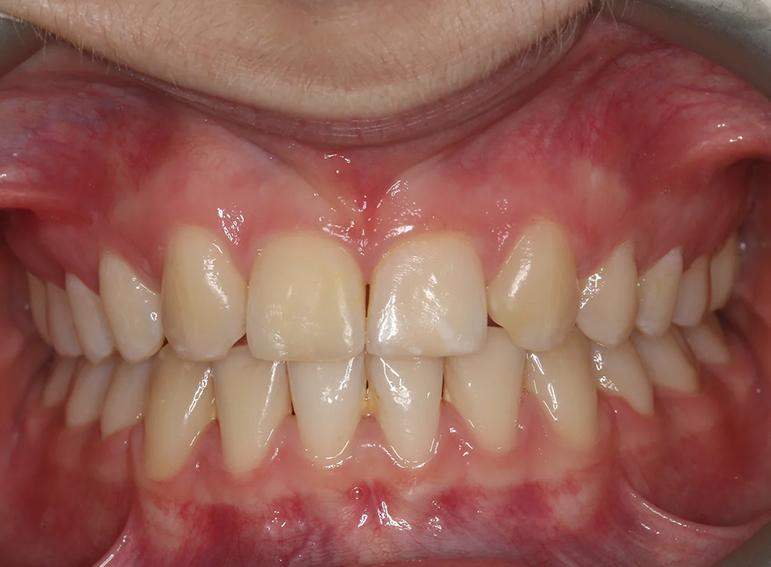

Gingival surgery and composite build up of an UR2 to resemble an UR1 following orthodontic treatment.